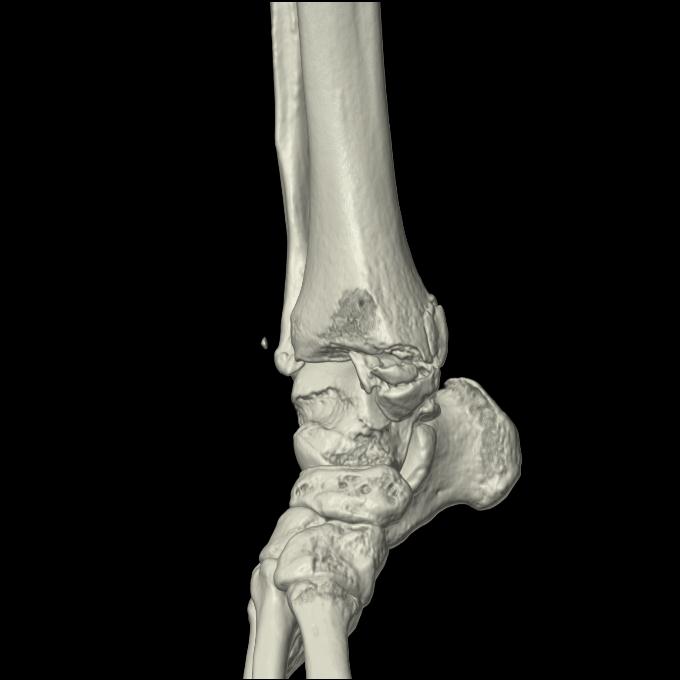

102755 1/4 2R 1/15 2R 右足関節 68歳女性 右三果脱臼骨折